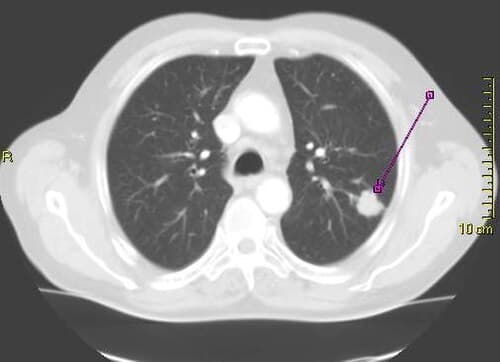

Long before a lung tumor becomes detectable on a scan, the cells that will eventually give rise to cancer are already engaged in a sophisticated arms race with the immune system. A new study has revealed the specific molecular mechanisms by which premalignant lung lesions evade immune detection, findings that could open the door to intercepting cancer at its earliest and most treatable stage.

The research, conducted by a multi-institutional team of oncologists and immunologists, analyzed tissue samples from patients with premalignant bronchial lesions, the kind of abnormal growths that sometimes progress to squamous cell carcinoma of the lung. While not all such lesions become cancerous, understanding why some do and others do not has been a central question in cancer prevention research for decades.